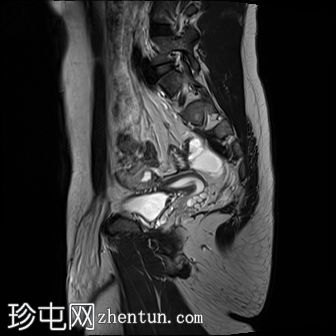

MRI

矢状位

T2

9.jpg

MRI图像显示子宫和睾丸。子宫内膜腔开口于前列腺尿道。

患者有双侧隐睾病史。CT和MRI图像显示发育良好的子宫和两个睾丸,均位于盆腔内。子宫内膜腔开口于前列腺尿道。

该患者表型为男性,阴茎发育良好。精液分析显示无精子症。结合影像学检查结果,最可能的诊断是持续性苗勒氏管综合征。这是一种男性假两性畸形,由子宫内抗苗勒氏管激素(AMH)分泌不足引起。AMH或其信号通路的缺乏导致苗勒氏管衍生结构的持续发育。